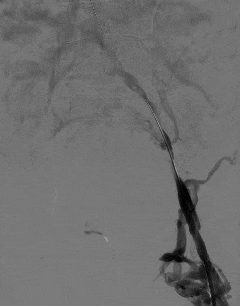

术中造影进一步确认,李叔叔左下肢深静脉全程闭塞,血流无法正常回流。

团队随即采用球囊扩张导管逐级对闭塞血管进行精准扩张,逐步恢复血管管腔通畅性。

术后即时评估显示,左下肢髂静脉恢复部分血流,肢体回流障碍得到有效改善。

李叔叔术后即刻反馈,左下肢憋胀感明显减轻,肢体比术前轻松了许多。